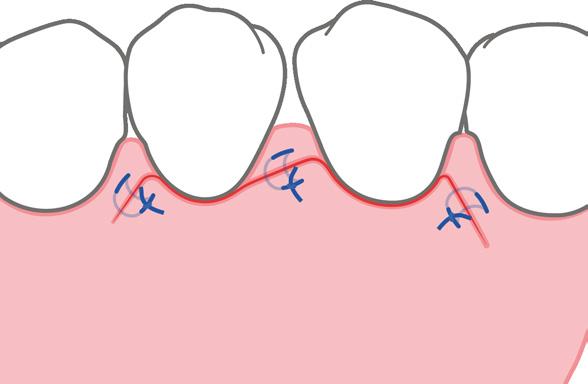

FASE PREOPERATORIA

FASE QUIRÚRGICA

incisiones verticales de descarga

granulación.

afectado (aproximadamente el 10 % de los casos), se añade Emdogain®

7. Cierre de la herida sin tensión con un colgajo de desplazamiento coronal. Sutura de colchonero horizontal y suturas adicionales en las incisiones verticales.

8. En caso de movilidad: los dientes se estabilizan mediante férulas removibles o no removibles.

2. 1. 3.

6. En defectos no contenidos se añade Geistlich Bio-Gide® Perio, sin sutura ni pins

Clorhexidina al 0,2 % 3 veces/día durante la cicatrización de la herida en el posoperatorio, opcional

No usar cepillos interdentales etc. hasta que el tejido queratinizado se haya regenerado

Retirada de la sutura 10-14 días después de la cirugía

Primeros 6 meses con visitas de seguimiento a intervalos breves y limpieza dental profesional sin instrumentación subgingival

Reevaluación (clínica y radiográfica) 1 año después de la cirugía, comienzo del tratamiento de apoyo sistemático personal

*Medicación antibiótica perioperatoria complementaria (p. ej. amoxicilina y metronidazol, según la predisposición del paciente y los hallazgos, opcional)

20 GEISTLICH NEWS 1-2021

FASE POSTOPERATORIA

Geistlich Bio-Oss® Collagen.

FIG. 1: Terapia periodontal regenerativa paso a paso